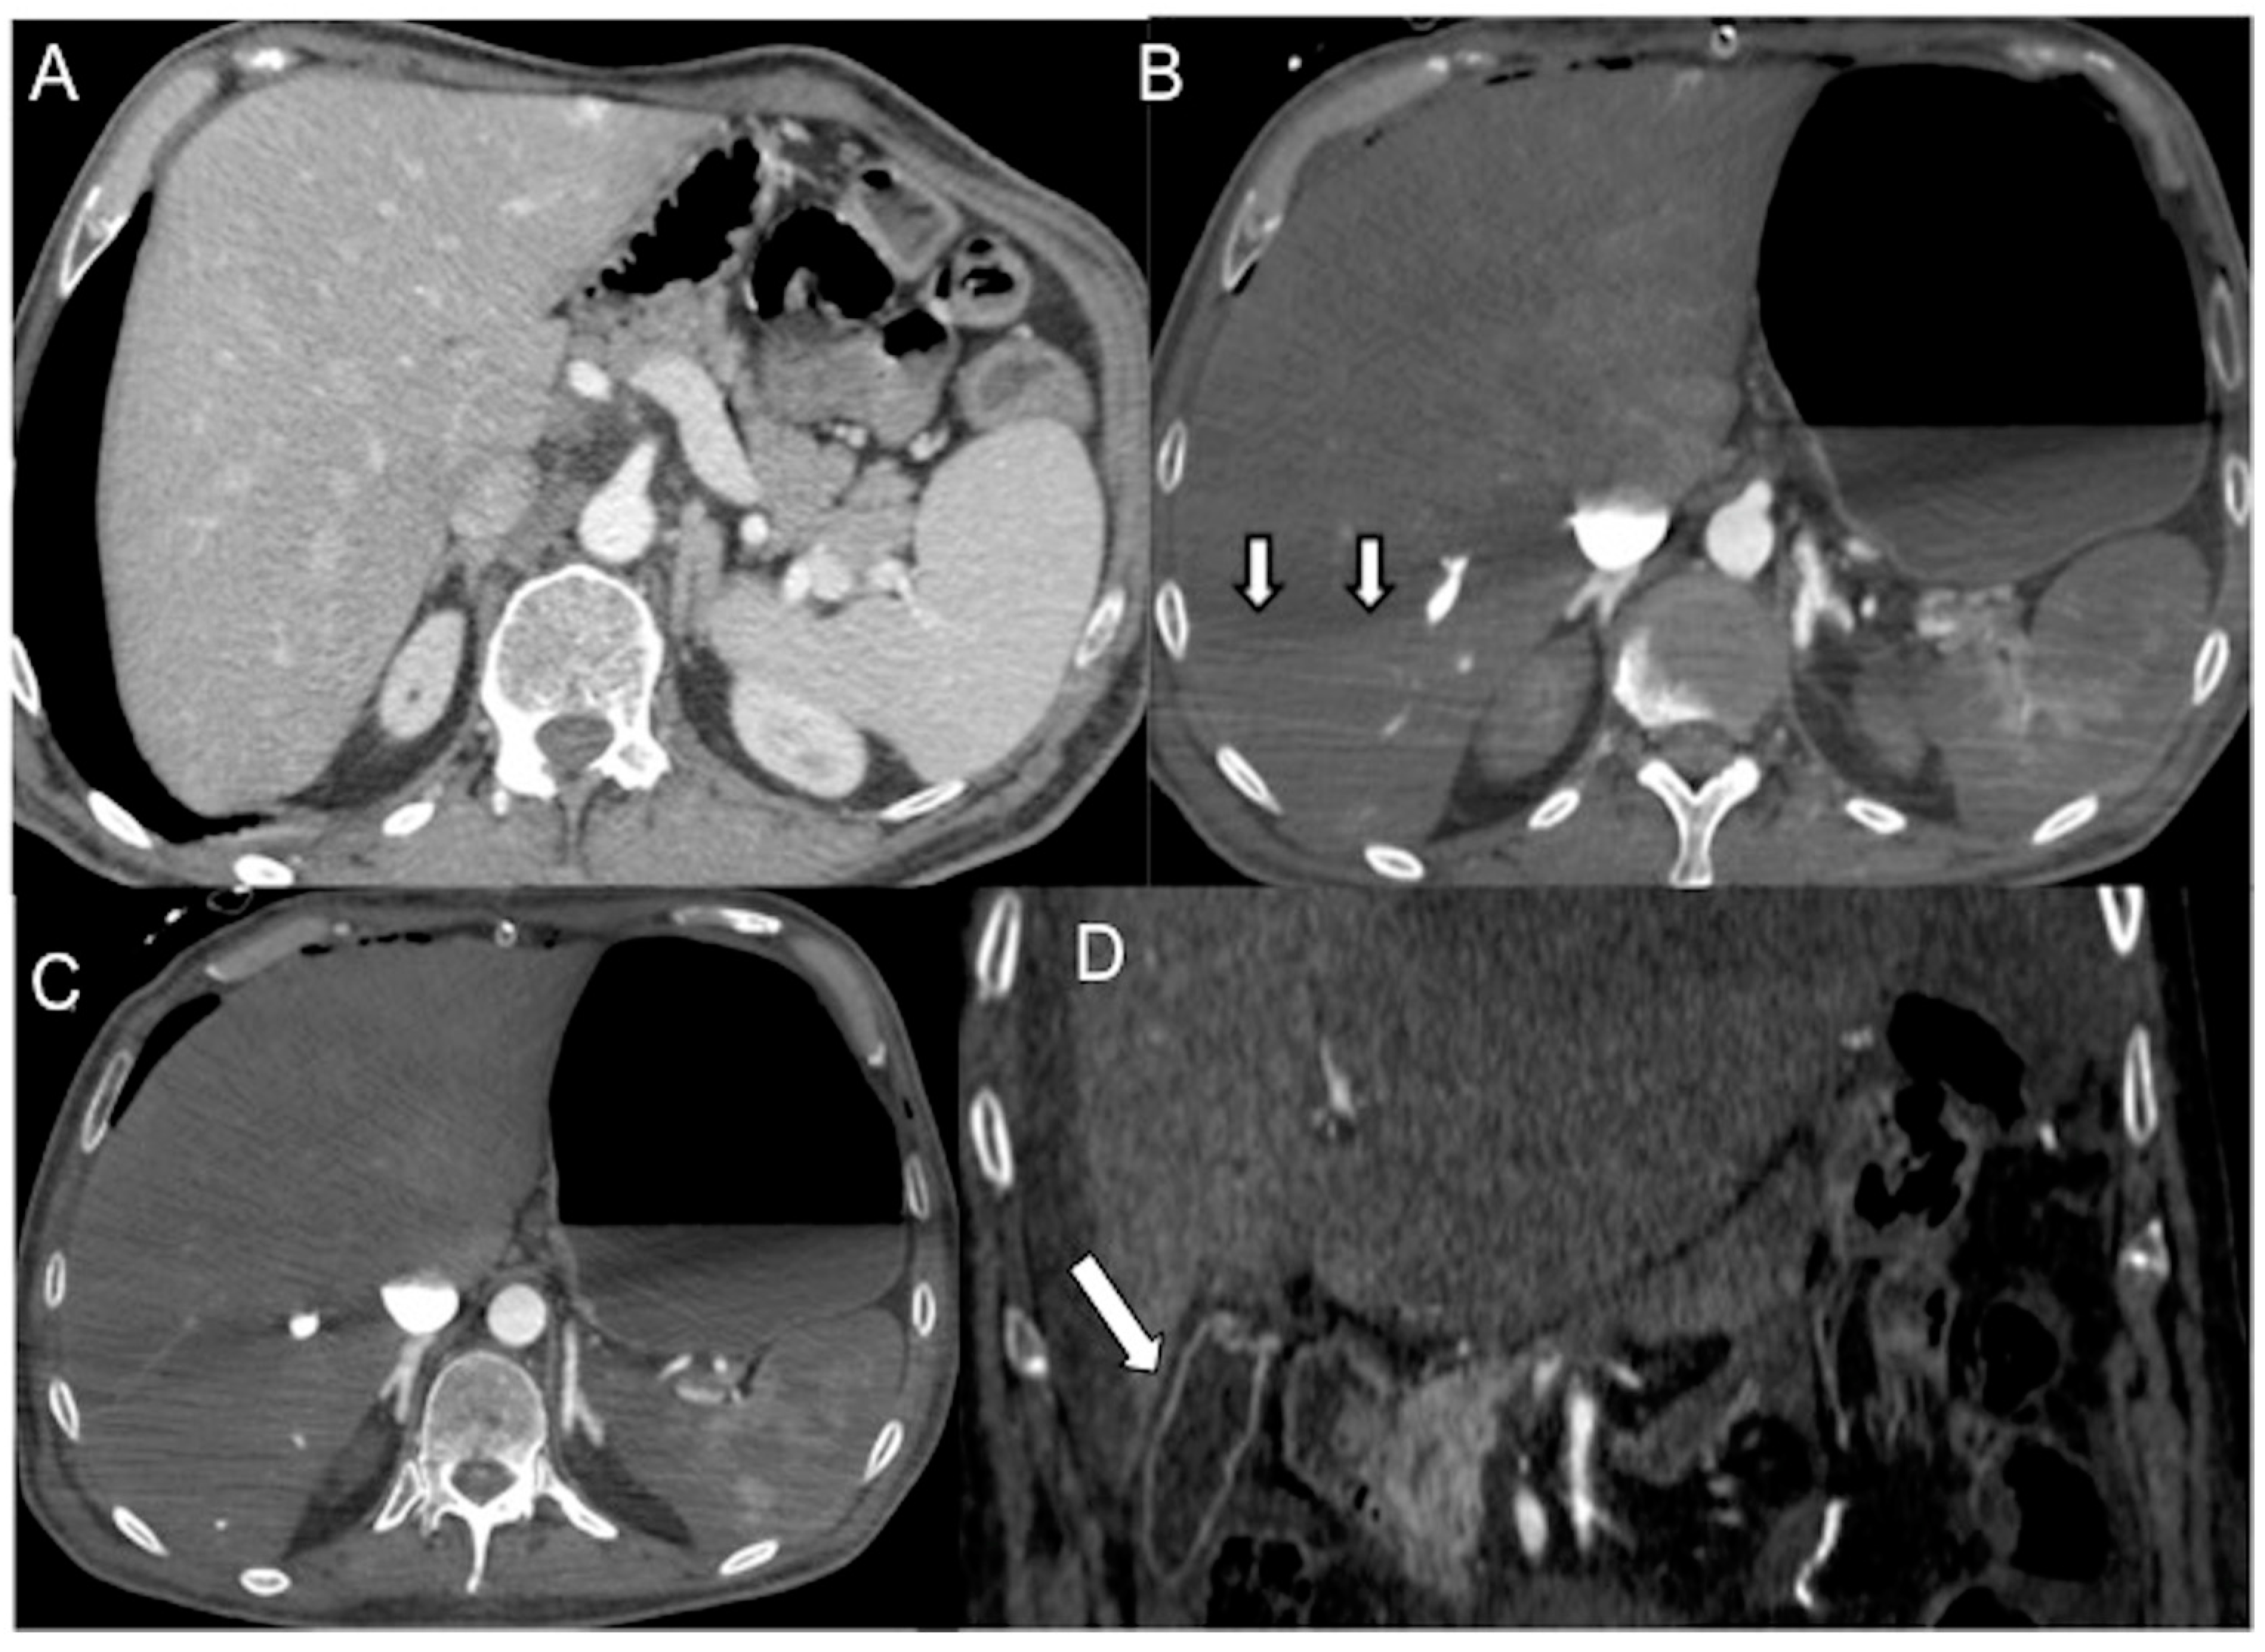

- The IVC halo sign is characterized by a low attenuation band (<20 HU) encircling the collapsed intra- and retrohepatic inferior vena cava. This band is caused by a ring or rim of edema [65,66,67]. In cases of severe hypovolemia, approximately 80% of patients may exhibit this sign, resulting from the loss of precapillary arteriolar sphincter tone and the accumulation of fluid surrounding the IVC (Figure 2B–D) [18,25,30,31,65,66,67]. However, it is important to note that this sign is not specific to non-traumatic patients and can also be observed in conditions such as liver congestion, biliary cirrhosis, hepatitis, or other diseases that obstruct lymphatic drainage at the porta hepatis [25].

- There is the presence of a slit-like or flat inferior vena cava (FIVC) (Figure 2A). This is characterized by an anterior-posterior diameter of less than 9 mm in three consecutive segments, 20 mm above and below the renal veins, and at the level of the perihepatic region. Additionally, a transverse-to-anteroposterior ratio of ≥2.5 at the level of the suprarenal IVC can indicate flattening. The flatness index or IVC diameter ratio is calculated by dividing the maximal transverse and anteroposterior diameters of the IVC [15,16,17,18,19,20,21,22,23,24,25,26,27,28,29,30,31,32,57,58,59,60,61].

- Flattening of the IVC (slit sign) is often seen in cases of decreased circulating blood volume (hypovolemia) and indicates reduced venous return in patients with systemic hypotension. However, it may not be easily appreciated due to the administration of large volumes of fluids [31]. This finding is more commonly observed in acute hypovolemic traumatic patients. Variations in intra-abdominal pressure and the respiratory cycle can also affect the diameter of the IVC. IVC flattening has a specificity of 90% and a sensitivity of 84% in identifying hypo-perfusion shock in spontaneously breathing patients [15,16,17,18,19,20,21,22,23,24,25,26,27,28,29,30,31,32,57,58,59,60,61,62,63]. The IVC diameter ratio measured via CT scans can help predict in-hospital mortality in septic shock patients, with a cut-off value of ≥1.3 cm having 75% sensitivity and 42% specificity [63]. It is also useful in determining the amount of blood transfusion required and assessing the volume status of patients with blunt torso trauma. [64].